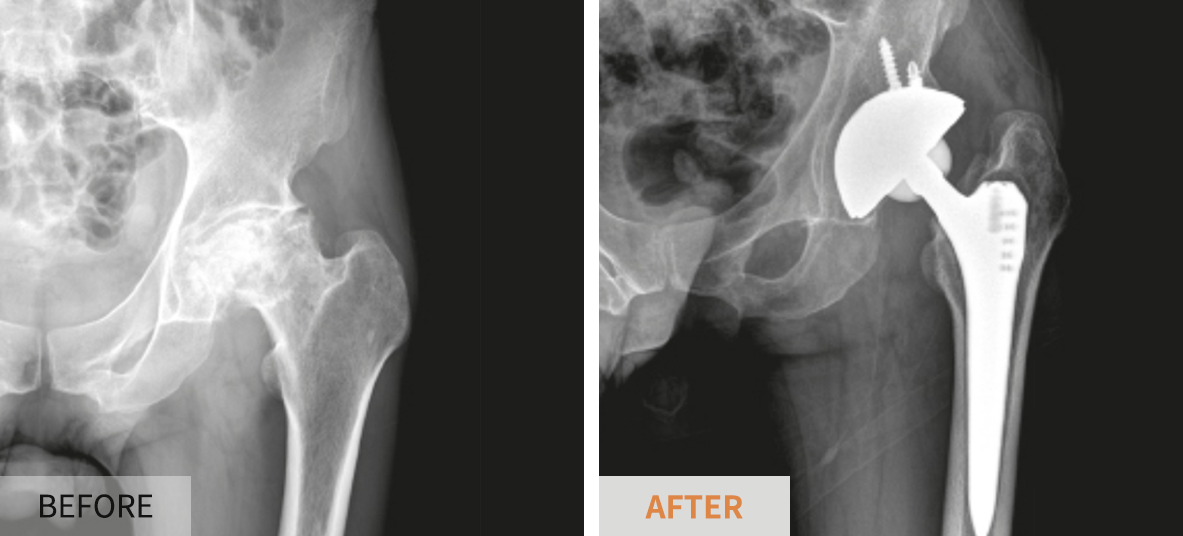

- 인공관절 치환술: 가장 일반적인 고관절 수술입니다. 퇴행성 관절염이나 심한 외상으로 인해 고관절이 손상된 경우, 인공 관절로 대체합니다. 이 수술은 대개 1-2시간 가량 소요되며, 회복이 길어질 수 있습니다.

각 수술 방식에 따라 환자의 상태를 고려한 특화된 치료 계획이 필요합니다. 예를 들어, 인공관절 치환술을 받을 경우에는 십여 주의 회복 기간 동안 물리 치료와 약물 치료가 반드시 포함되어야 합니다. 반면 관절경 수술의 경우에는 초기 회복 단계에서의 가벼운 운동과 체중 부하가 더 강조될 수 있습니다.